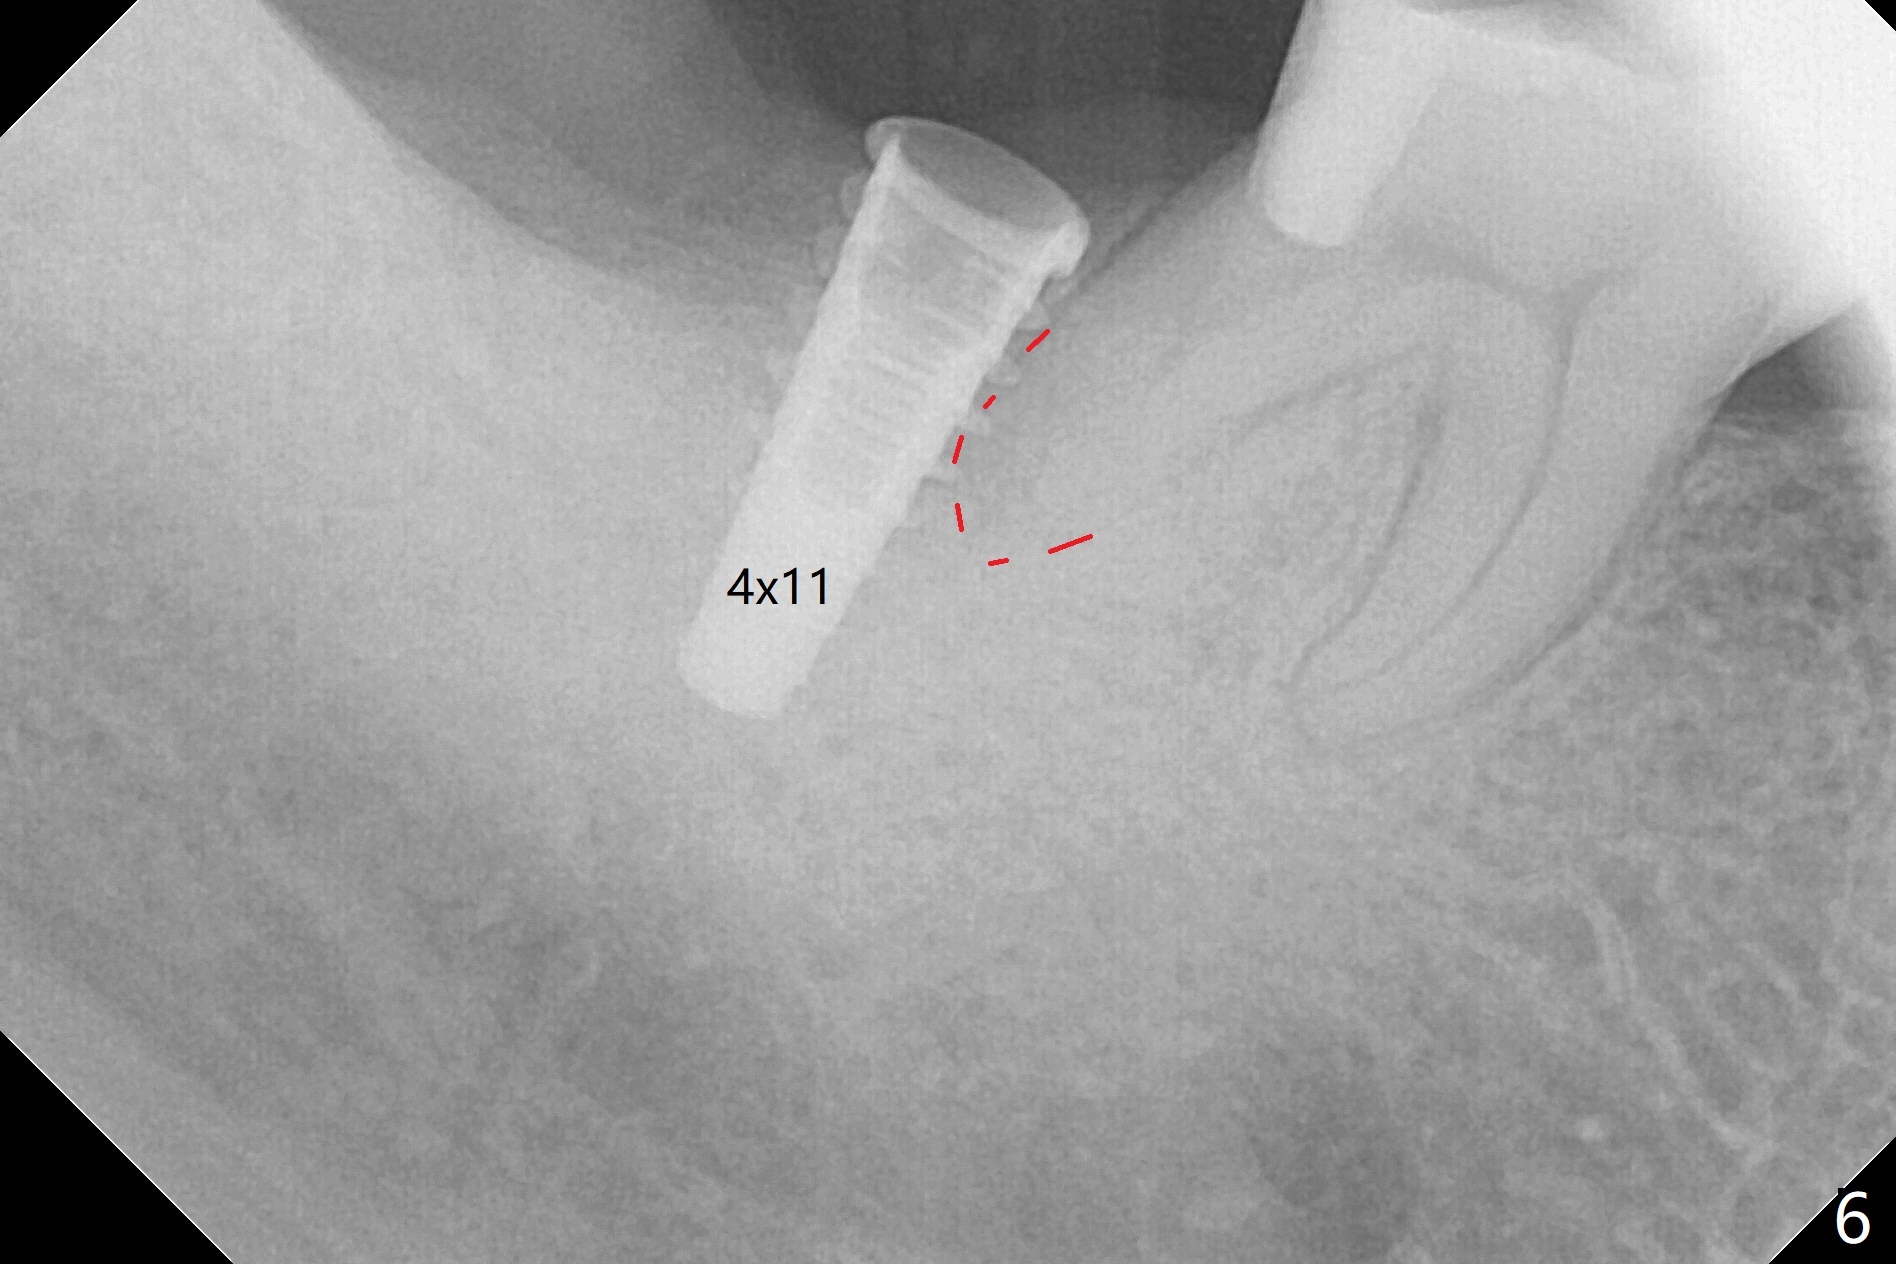

The socket shrinks with buccal plate reduction 3 months post socket preservation (Fig.5), as compared to 10 days postop (Fig.4). To restore the socket as much as possible, Magic Split is used (flapless), followed by Magic Expanders 3-3.8 mm for 11 mm (gingival level) and a 4x11mm dummy implant (Fig.6). The osteotomy is moved distal by using Lindamann bur; following 3.8 mm Magic Drill, a 4.5x11 mm dummy implant (Fig.7). Finally a definitive 5.5x9 mm implant is placed with <45 Ncm; a 6x2 mm healing abutment is placed to close the access (Fig.8). Autogenous bone harvested from the Magic Drill returns to the osteotomy mainly buccal prior to implant placement (Fig.8 *). The patient reports no discomfort immediately postop, thanks to the flapless technique. The patient has had postop pain; 11 days postop, the abutment and implant are found to be loose. After re-tightening by hand, the complex is seated deeper and more stable (Fig.9 arrow).